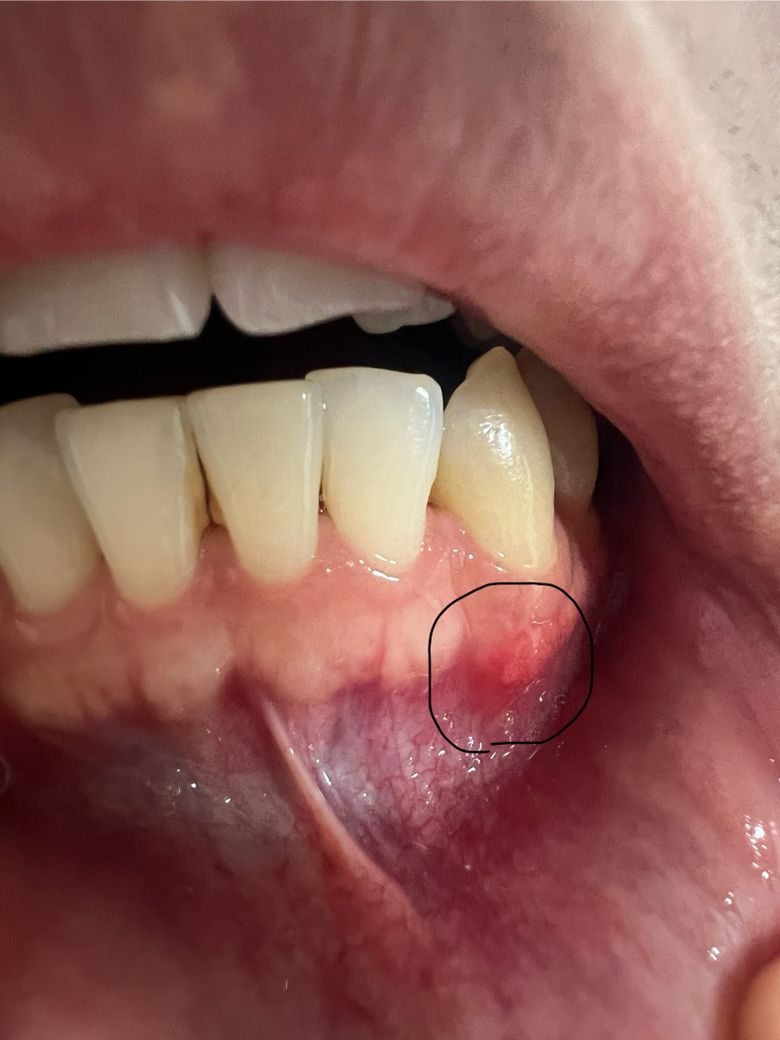

잇몸에 뾰루지 같은데 낫던데 염증생긴겅가요?

잇몸에 뭔가 불편감이 있어서 보니까 뾰루지 같은게 낫던데 염증난건가요

가만히 있으면 통증이나 뭐 그런게 없어서 잘모르겠는데 건들면 통증이 좀 있네요

• 1번 째 사진

단순 구내염이 생긴 것으로 보이지만 1주일 정도 지켜보시고 사라지지 않으면 치과 가보시는 게 좋습니다.

염증은 아닌거 같고 잇몸부위가 자극을 받아서 물집이 잡힌거 같습니다. 통즈잉 없다면 크게 걱정하지 않으셔도 됩니다.

현재 잇몸에 염증이 있어 보이며,치석이 있는 경우 잇몸을 자극하여 잇몸에 염증을 유발할수 있습니다.

통증이 더 심해지거나, 해당 부위가 붓거나, 고름이 나오는 경우 치과에 방문하여 상태를 확인하고, 스케일링 및 염증치료를 받길 권합니다.